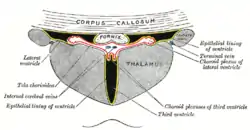

Drawing of a cast of the ventricular cavities, viewed from above. View of ventricles and choroid plexus

View of ventricles and choroid plexus Lateral ventricles along with subcortical structures, in glass brain